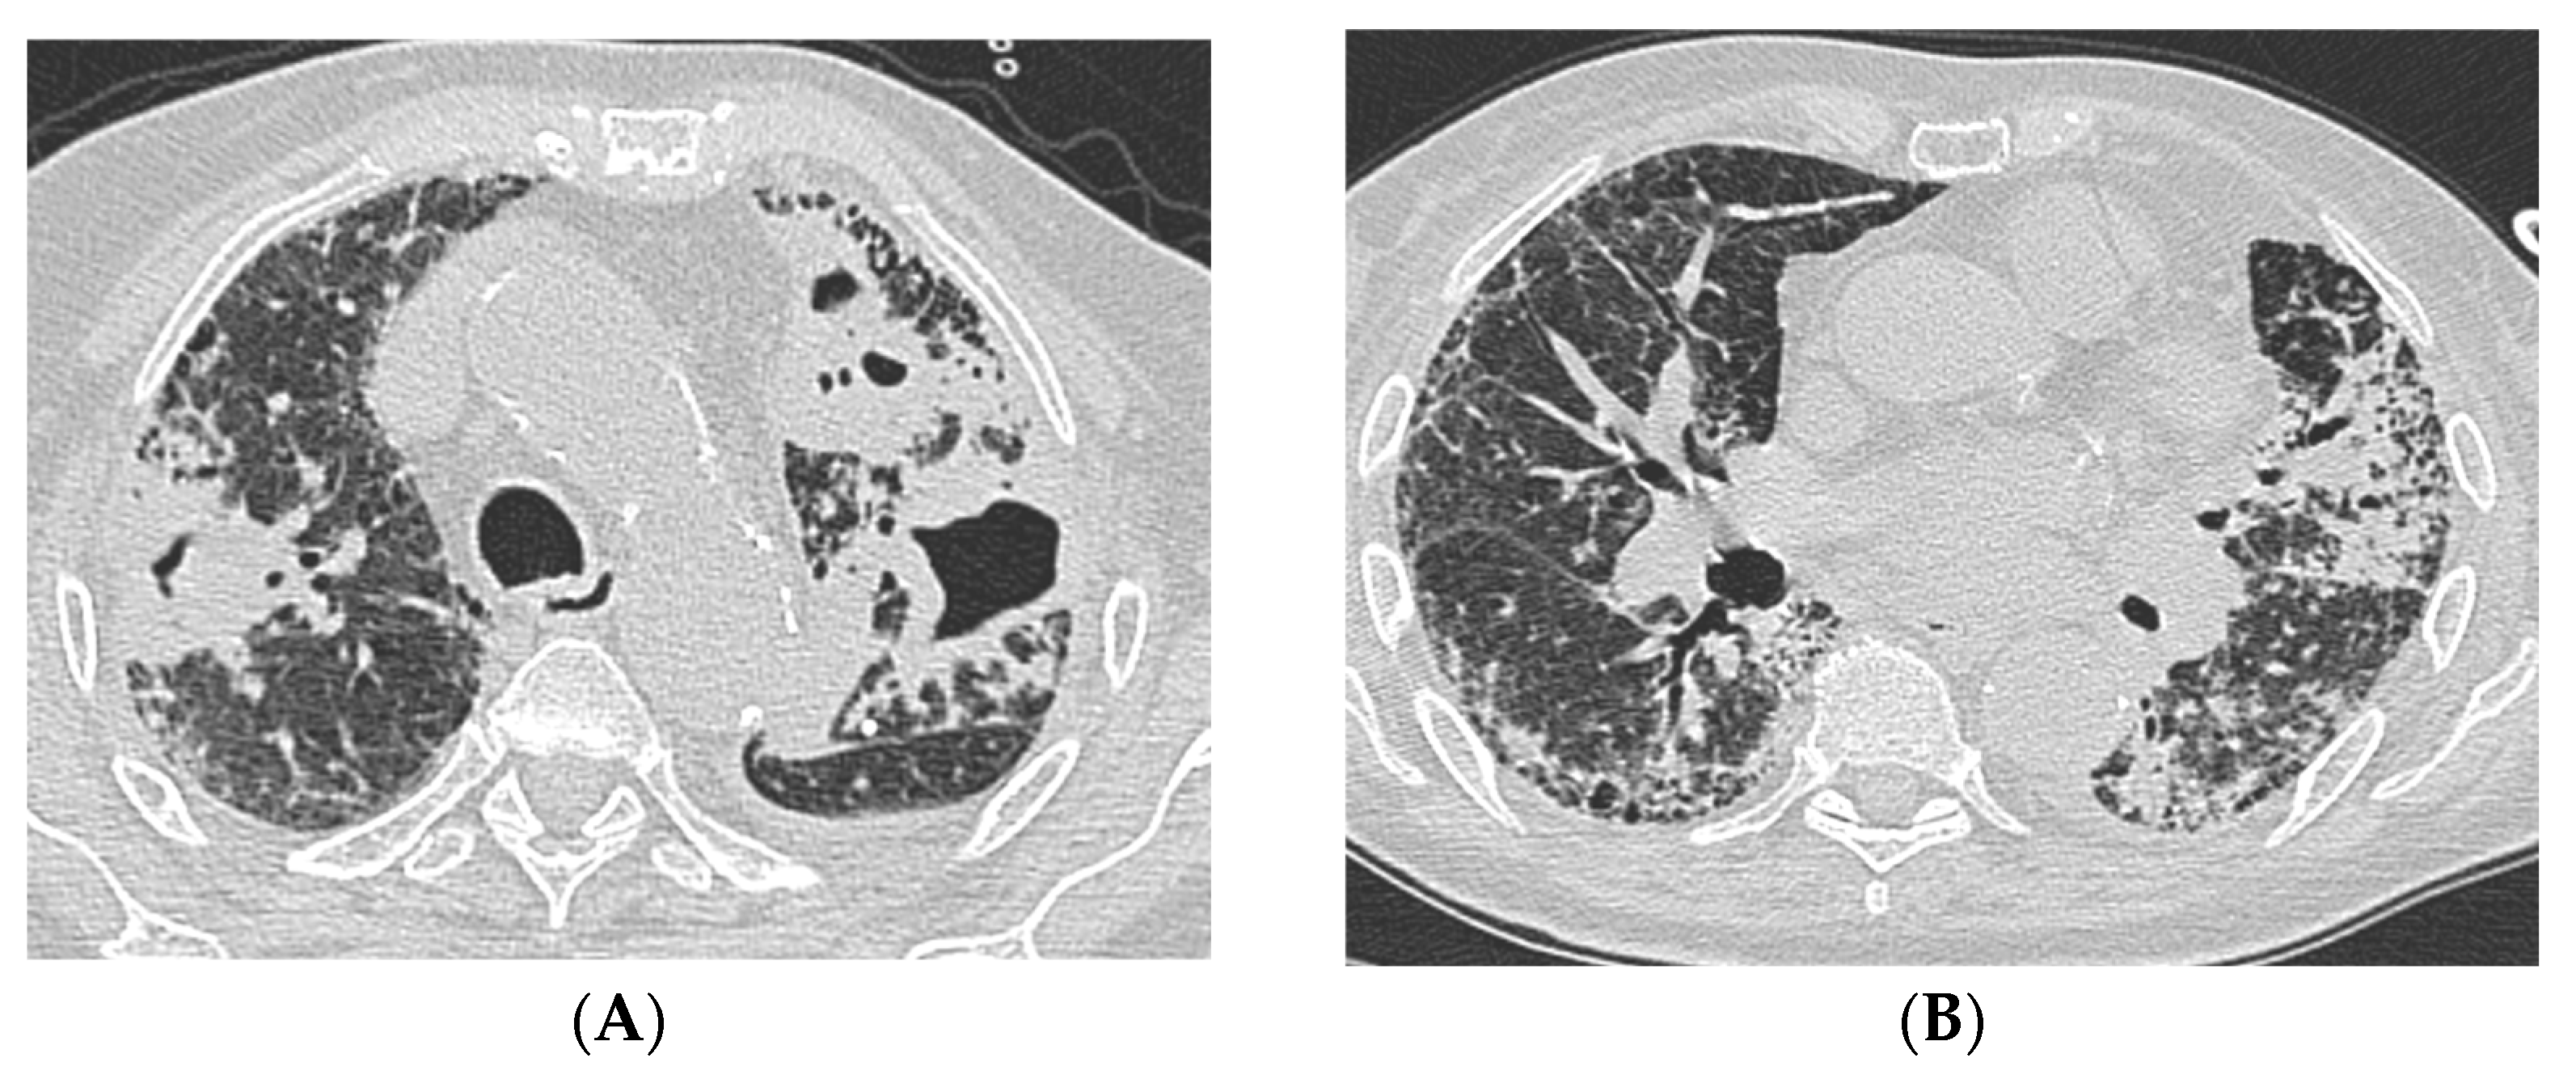

A 76-year-old male, a former smoker, with a three-year history of connective tissue disease-associated interstitial lung disease (CTD-ILD) classified as rheumatoid arthritis (RA) with a UIP at chest HRCT, as adjudicated by multidisciplinary discussion (MDD), managed with azathioprine and long-term oxygen therapy, was referred to the Emergency Department with massive hemoptysis. Upon admission to the emergency department, the patient presented with hypoxemic hypercapnic respiratory failure that required oxygen therapy via Venturi mask with a fraction of inhaled oxygen (FiO2) equal to 40%. Laboratory tests revealed significantly elevated inflammatory markers and anemia, with a hemoglobin level equal to 8 g/dL, necessitating a transfusion of two units of packed red cells. Therefore, an urgent contrast-enhanced chest CT scan was performed; it demonstrated the presence of UIP pattern and bilateral cavitary lung consolidations, of which the most extensive was located in the right lower lobe (Figure 1). Conversely, no active sources of bleeding were identified. Following hemodynamic stabilization, a bronchoscopy with bronchoalveolar lavage (BAL) was performed to further evaluate the pulmonary findings at chest HRCT; while endobronchial blood clots were removed, no active signs of bleeding were observed. Then, the patient was administered broad-spectrum empirical antibiotic therapy with piperacillin-tazobactam and vancomycin, despite the absence of microbiological results. The bacterioscopic assessment of the BAL fluid tested positive for acid-fast bacilli, while the polymerase chain reaction (PCR) for Mycobacterium tuberculosis (Mtb) was negative. Additionally, PCR testing confirmed the presence of Mycobacterium kansasii, which was further confirmed by microbiological culture. The administration of antibiotic therapy improved clinical status and gas exchange by reducing FiO2 from 40% to 24%. The patient started a targeted antimicrobial therapy with rifampin, azithromycin, and ethambutol, which was well-tolerated, leading to the patient’s discharge with oxygen supplementation only during physical exertion. Symptoms such as persistent catarrhal cough, hemoptysis, low-grade fever, and weight loss gradually resolved after six months of therapy. Hence, the case underwent a second MDD, and although criteria for progressive pulmonary fibrosis (PPF) were identified, antifibrotic therapy with nintedanib was not initiated due to the higher risk of iatrogenic hepatitis associated with concomitant rifampin use. Eventually, antifibrotic treatment was not initiated and deferred until the completion of antimycobacterial therapy, which lasted 12 months from the date of negative sputum cultures, for a total of 18 months.

Figure 1. Case #1 contrast-enhanced CT scan acquired in the emergency room during massive hemoptysis. UIP pattern is evident in the lower lobes (A), while the most extensive consolidation is located in the apical segment of the right lower lobe (B). Abbreviation: CT, computed-tomography; UIP, usual interstitial pneumonia.